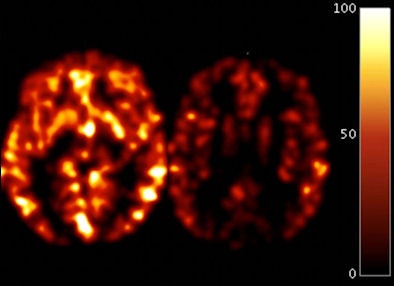

| Image shows two axial scans of blood flow with CASL MRI in two individuals. One is from a control subject (left) and one is from a person with Alzheimer's (right). The color bar shows blood flow corresponding to mL of blood per gram of tissue per minute. In Alzheimer's disease, there is reduced blood flow throughout the brain, which occurs early in the disorder. Image courtesy of Cyrus Raji, Ph.D. |

Four readers evaluated CASL scans visually to classify them as normal or abnormal based upon the appearance of lower regional cerebral blood flow in regions known to be affected by Alzheimer's disease. The analyses included images of the frontal, temporal, and parietal lobes and the cingulated gyrus.

All subjects were imaged with the CASL technique at 1.5-tesla MRI, which provides information on regional cerebral blood flow. SPGR 1.5-tesla MR images were conducted to visualize the subject's hippocampus structure.